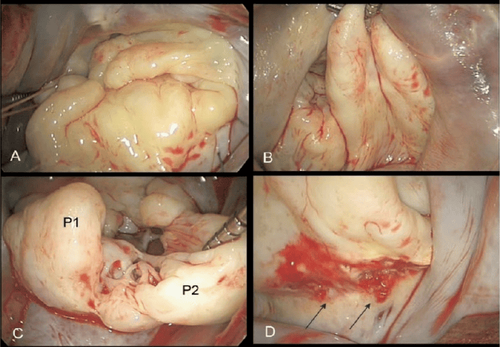

Tổn thương đại thể van 2 lá trong bệnh Barlow